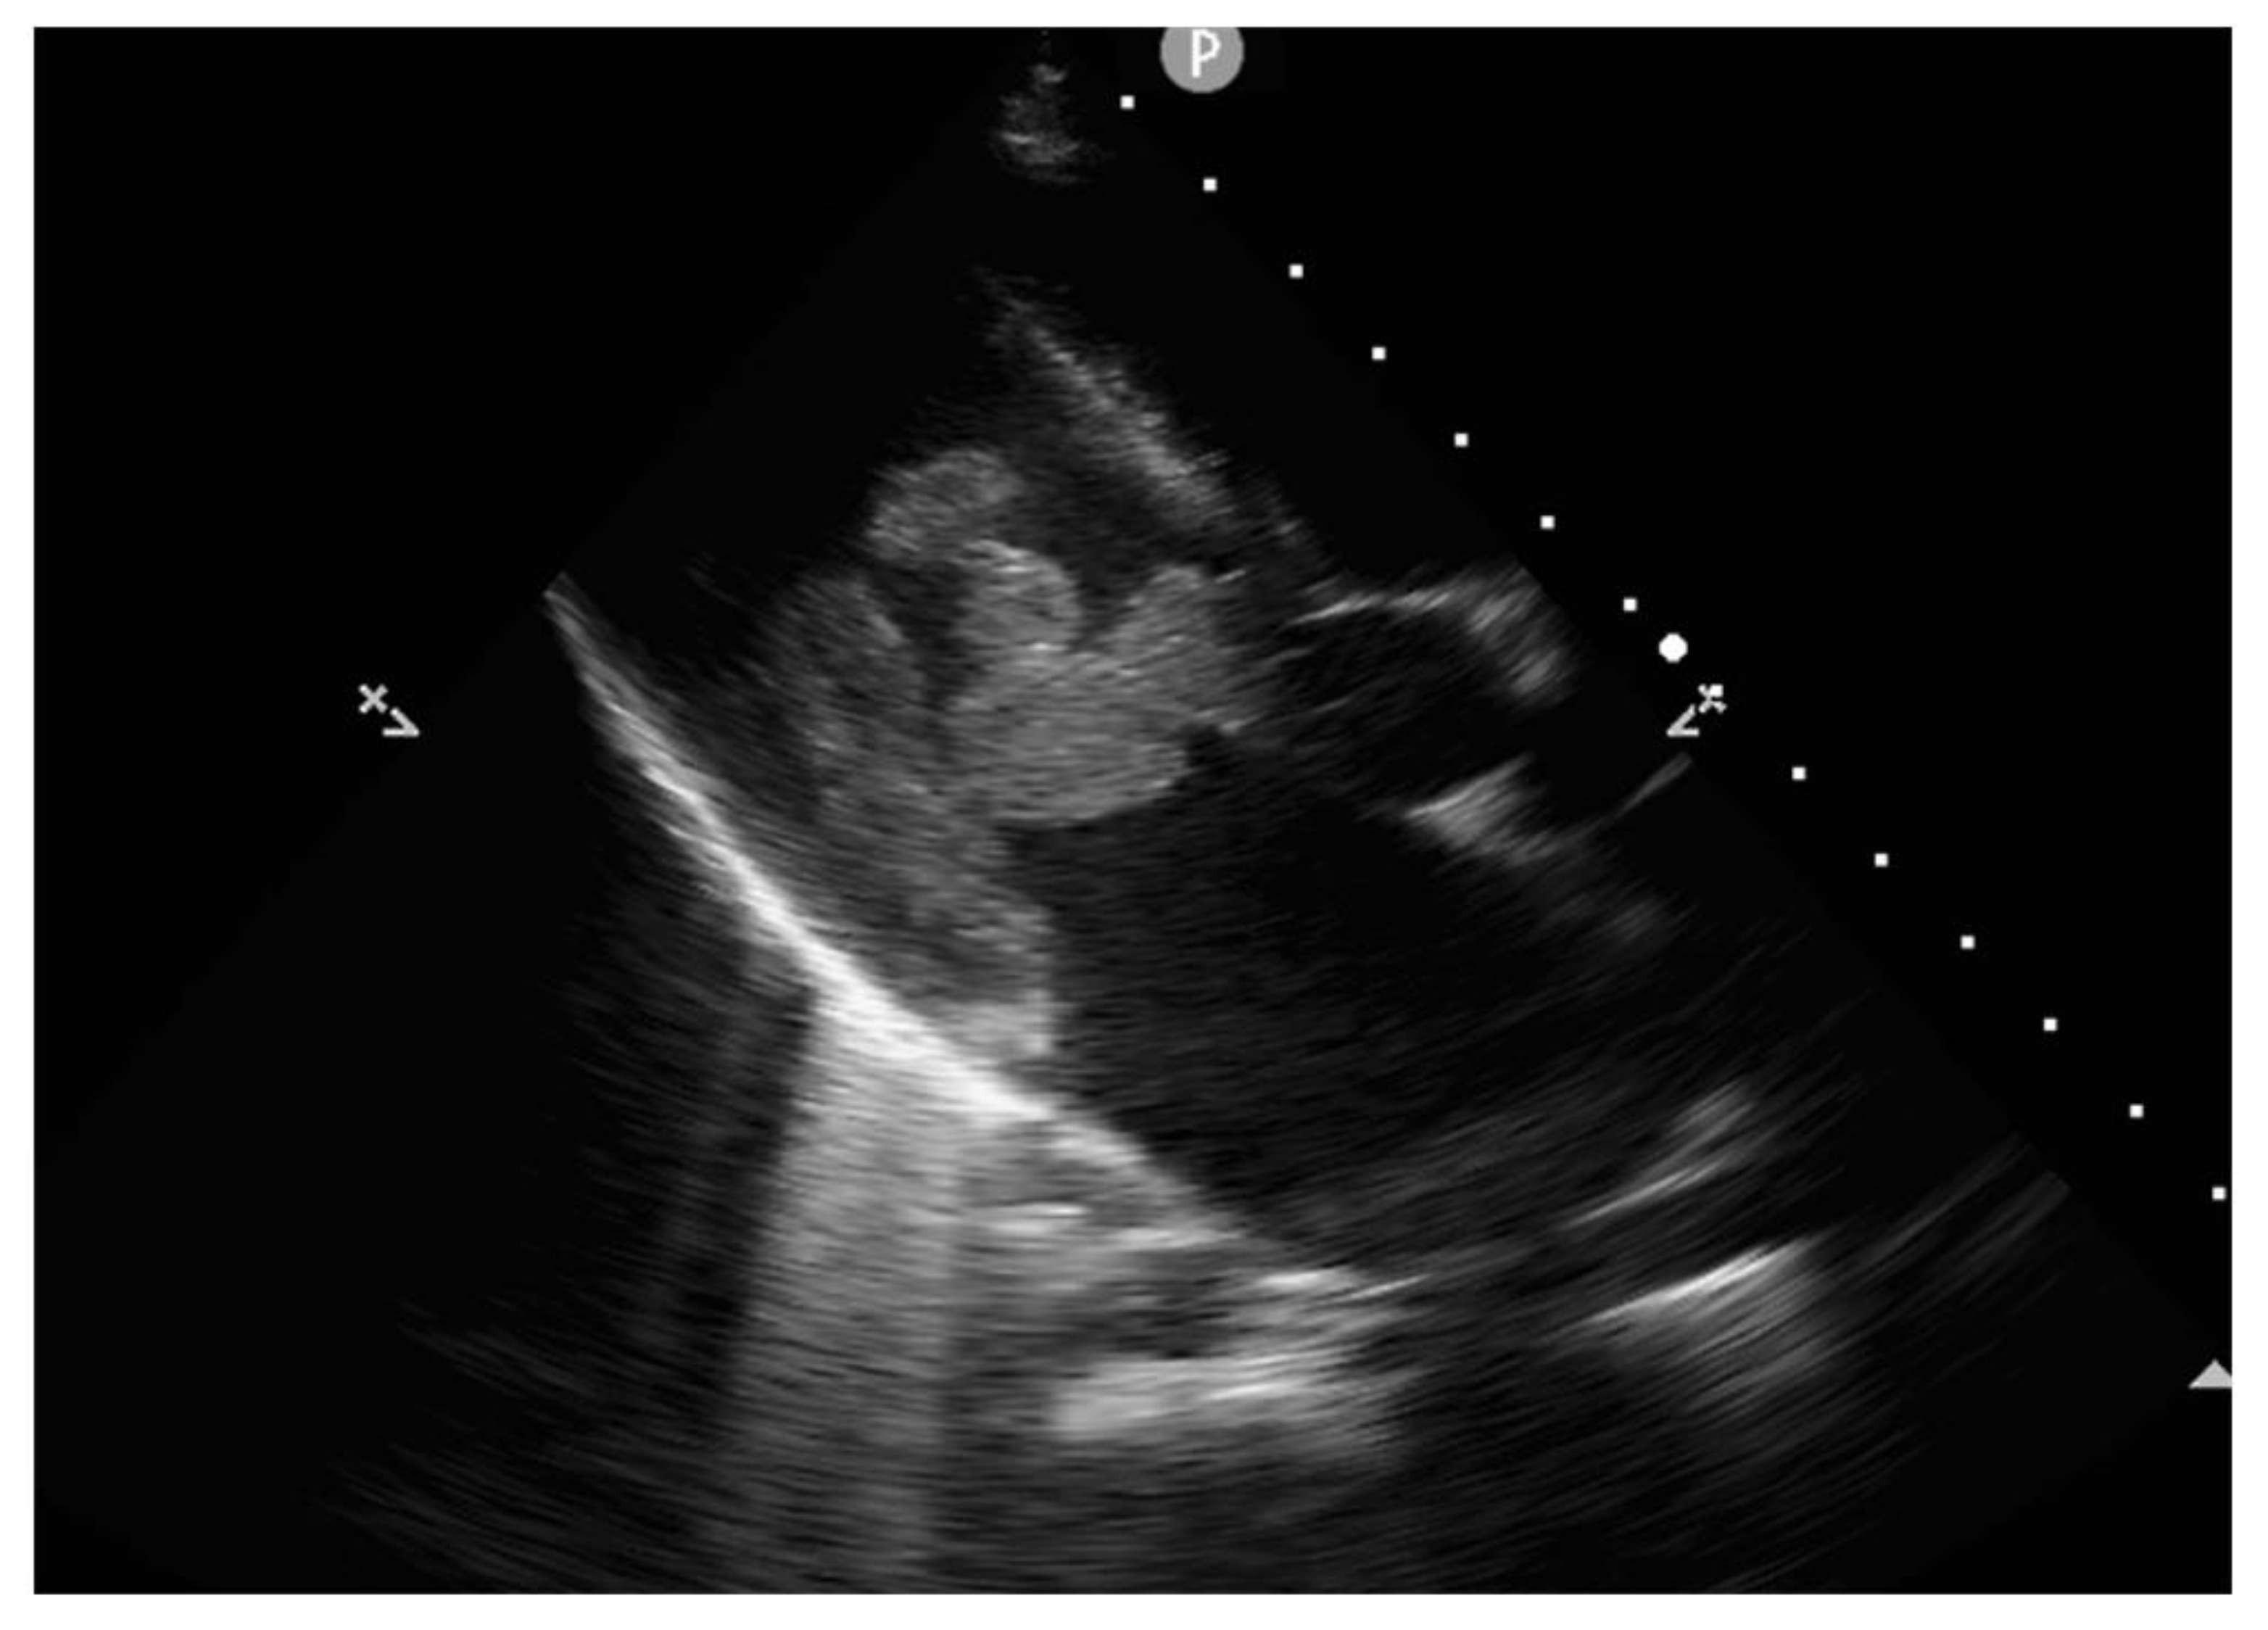

2. Case Report